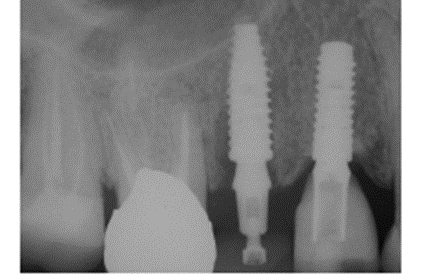

Foi eleito um implante Veloce Cone Morse de 3.75 X 11.5 mm e após a exodontia, o implante foi instalado utilizando o protocolo de fresagem recomendado pelo fabricante, fazendo uso das fresas escalonadas do sistema, alcançando um torque de inserção de 70 Ncm, o que me incentivou a promover o carregamento imediato deste implante (Figuras 5, 6, 7, 8, 9 e 10).

Diante das circunstâncias, foi eleito um pilar Ideale reto de 3.3 X 4.0 X 1.5 mm de transmucoso, que foi instalado a 20 Ncm. O escaneamento desse pilar foi realizado para a confecção de um provisório fresado em PMMA. Após 15 minutos da instalação e do escaneamento do pilar, o provisório fresado foi instalado sobre o pilar Ideale e aparafusado com o parafuso Torx a 10 Ncm. Foi então realizada uma radiografia após a instalação e a paciente foi marcada para retornos de 7 e 15 dias, sendo que após os retornos, a paciente realizou sua viagem (Figuras 11, 12, 13 e 14).